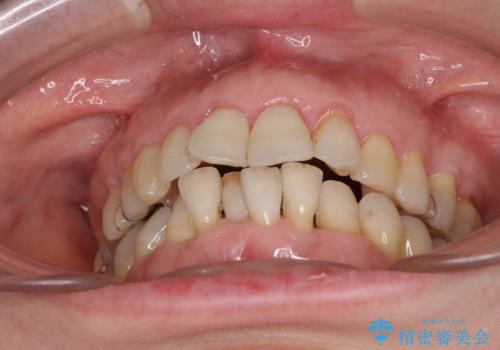

口元の出っ張りとデコボコを改善したい

- 近医にてインプラント治療を行った後に矯正治療を希望され、来院された患者様です。

口元の突出感とデコボコが気になっているとのことでしたが、インプラントが既に3本埋入されていたため、抜歯矯正による口元を引っ込めることができない状況でした。

近医での歯周病治療の影響でブラックトライアングルが発現していたため、IPR(歯と歯の間を削る)で隙間を改善しつつ、インプラントを固定源に歯列全体を後方へ移動させることとしました。